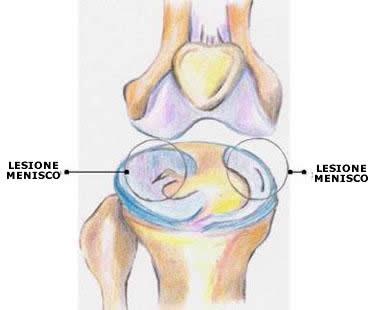

Si verifica tale situazione allorchè si lesiona quella parte del ginocchio, che consiste in una struttura cartilaginea situata tra femore e tibia, la cui funzione è quella di distribuire meglio il carico sull’articolazione e determinare il funzionamento del movimento. Se, insieme alla rottura del menisco, si verifica anche la rottura dei legamenti del ginocchio o del crociato, la gravità è sicuramente peggiore. La rottura del menisco può essere mediale o laterale. Sintomatologia del fenomeno è sicuramente il dolore insieme al rigonfiamento topico. Il dolore, nel caso del menisco mediale, è avvertito nella parte interna del ginocchio; nel caso del menisco laterale, invece, il dolore è localizzato esternamente. In ambedue i casi si verifica un cedimento ed anche un blocco dell’articolazione del ginocchio. Ciò avviene perché frammenti di menisco si inseriscono nelle parti che determinano la mobilità del ginocchio. Se avviene una pressione o una rotazione, il dolore tende ad aumentare e non si può estendere l’articolazione completamente. Inoltre viene prodotto del liquido, che si va ad accumulare nell’articolazione, a causa dell’infiammazione. L’articolazione subisce uno scricchiolio, oltre ad una perdita di forza del quadricipite.